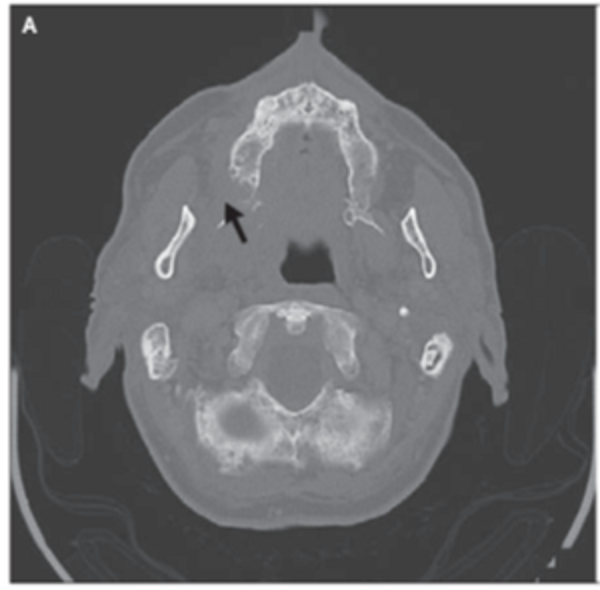

【下頜骨壞死】

ONJ於2003年首次報導在接觸BP的患者中

定義與BP相關的ONJ的三個要素包括:

1. 頜面部暴露和壞死骨的存在,在8週內不癒合

2. 當前或過去接觸BP

3. 先前放射治療在顱面部區域的負面病史

發生ONJ的風險與治療持續時間累積劑量成正比,並且還受到所用BP的給藥途徑效力的影響。

ONJ在骨鬆患者發生率屬罕見。發生風險約為每10萬個Patient-Treatment Years發生一例。

下巴頜骨壞死(ONJ):在惡性腫瘤(骨轉移,惡性高鈣血症等)的治療中,雙膦酸鹽治療劑量比骨質疏鬆症治療的劑量高幾十倍,與骨壞死風險增加(高達1%)有關。

實際上,已經發現它是一種骨髓炎,幾乎總是與放線菌(Actinomyces)感染有關。

據報導,對於骨質疏鬆症治療的患者,雙磷酸鹽治療的這種不良反應的頻率較低,並且在涉及骨暴露的口腔侵入性手術後風險增加(小魏醫師記得七成以上與拔牙有關)。